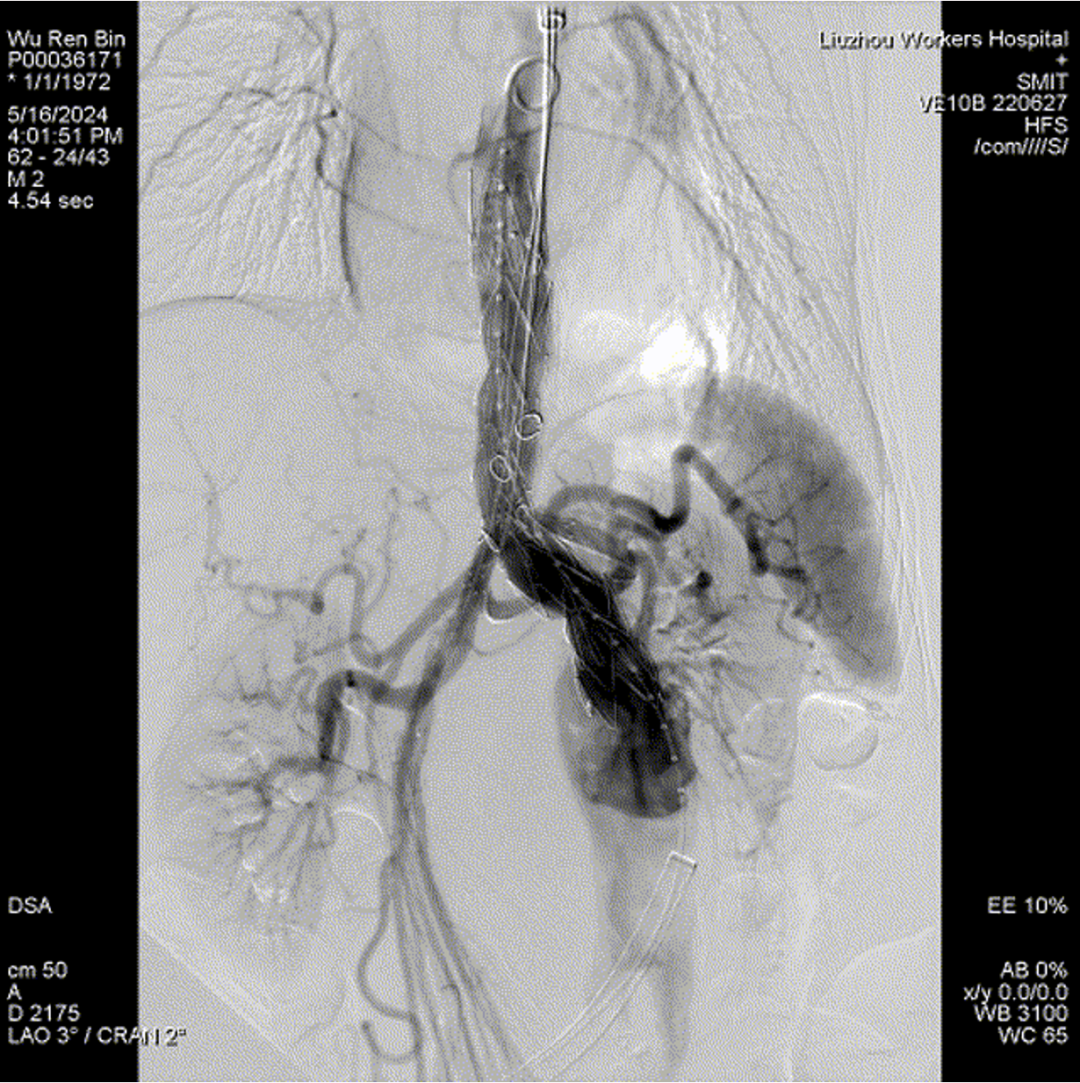

四分支重建后造影,各分支血流通畅

病例2:f-TEVAR(双3D技术,体外三开窗重建弓部三分支)

术前造影

术中3D影像引导,主体支架精准定位

3D影像引导下,

主体支架窗口与弓上三分支开口对位

依次超选无名、左颈总及左锁骨下动脉

术后造影,支架形态良好,分支血流通畅